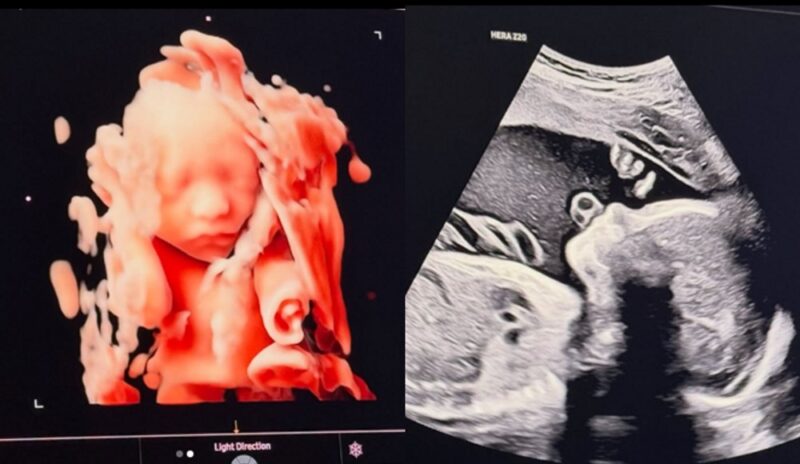

ソン・スンヒョンは21日、自身のSNSアカウントを通じて「もうすぐ会おう、私たちの太陽」という短いメッセージと共に、胎児の姿が写った写真2枚をアップロードしました。公開された写真は3D立体超音波で撮影されたもので、まだこの世に生まれていない子どものはっきりとした目鼻立ちが、見る人の視線を引きつけています。